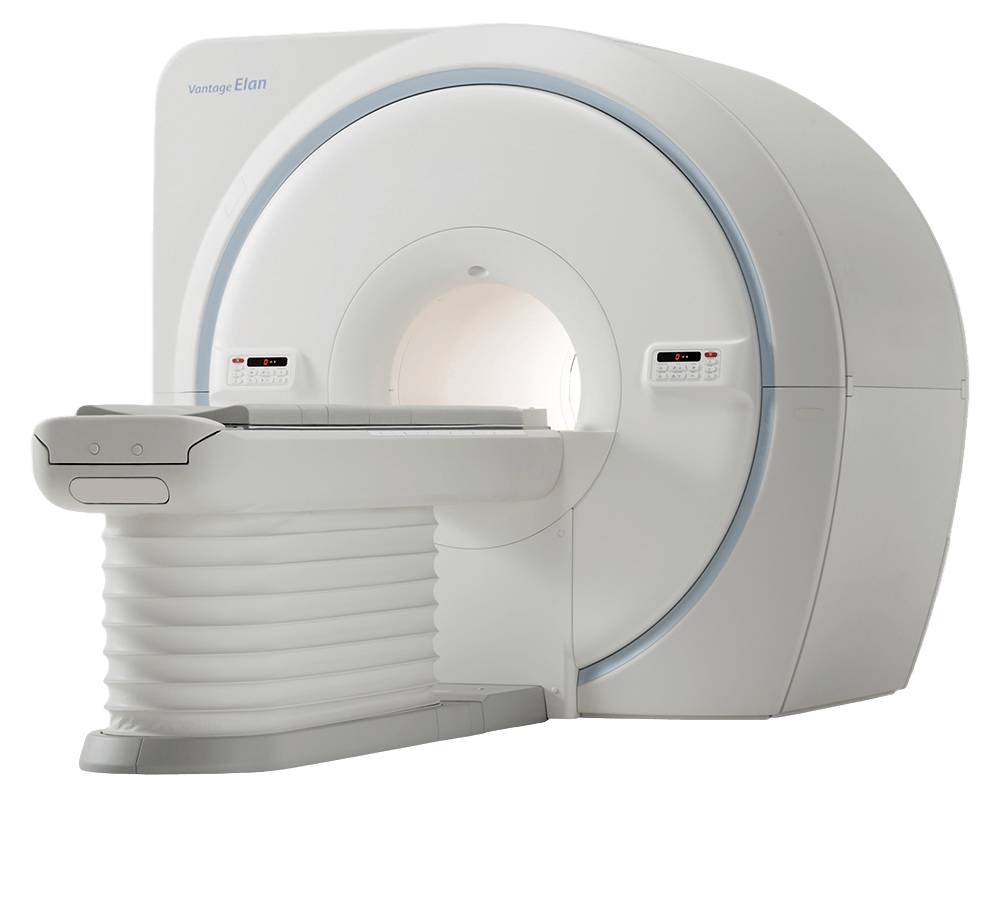

Vantage ELAN – это магнитно-резонансный томограф со встроенной системой охлаждения и низким энергопотреблением.

При разработке сканера для МРТ Vantage ELAN компания Canon уделила особое внимание контролю за магнитным полем. Как следствие, была разработана система Advanced Magnet, генерирующая высокооднородное статическое магнитное поле, от которого зависит качество получаемых изображений. В томографе применяется такой же магнит, как и в экспертных томографах.

Новая градиентная катушка Canon Advanced Gradient Shielded Coil System за счет экранирования минимизирует вихревые токи и улучшает качество снимков.

Технология Pianissimo снижает акустический звук во время сканирования и повышает комфорт исследования для пациентов.

Инновационный комплект катушек с уменьшенным количеством элементов без потери качества. Радиочастотная система томографа улавливает и усиливает сигналы от тела пациента и передает их с минимальным шумом.

- Большой диаметр апертуры и короткий канал

- Высокая однородность поля

- Цифровая РЧ система

- Беспроводные системы синхронизации

- Матричная концепция катушек

- 18 кВт энергопотребления

- 23 м² площадь установки